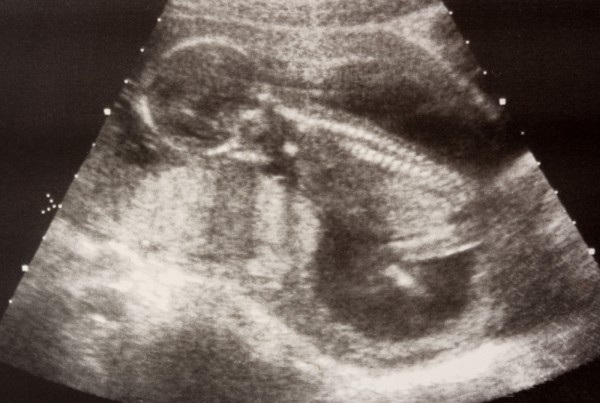

УЗИ

С 16 по 20 неделю беременности женщина проходит второе скрининговое обследование, которое включает ультразвуковое исследование и лабораторные анализы. Это обследование позволяет оценить жизнеспособность плода, его развитие и выявить возможные патологии.

Во время ультразвукового исследования можно определить пол ребенка, так как наружные половые органы уже сформированы. Однако иногда это затруднительно, если малыш закрывает себя ручками или занимает неудобное положение.

На шестнадцатой неделе, при необходимости, проводится допплерометрия. Это исследование оценивает кровоток в пуповине и позволяет выяснить, получает ли плод достаточное количество питательных веществ и кислорода от матери.